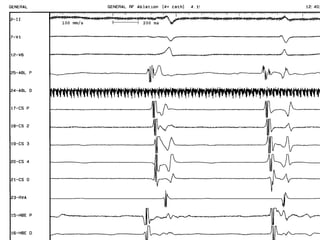

Normal sequence ofNormal sequence of

retrograde activationretrograde activation

earliest at the Hisearliest at the His

bundle electrogram-bundle electrogram-

(1st), otherwise(1st), otherwise

accessory pathwayaccessory pathway

exists e.g if earliest inexists e.g if earliest in

the CS (2nd,3rd).the CS (2nd,3rd).